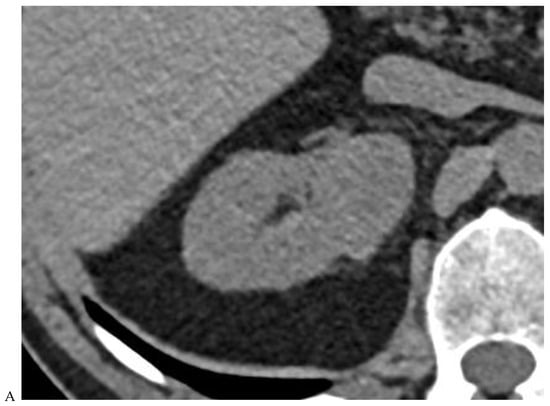

Figure 4.

Multiphasic CT enhancement of a papillary renal cell carcinoma in the middle part of the right kidney of a 63-year-old woman. (A) Mean unenhanced attenuation was 35 HU. (B) Mean corticomedullary phase attenuation was 45 HU. (C) Mean nephrographic phase attenuation was 59 HU. (D) Mean excretory phase attenuation was 65 HU.